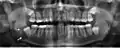

Галерея

Панорамная рентгенограмма, показывающая дефект Стафне (отмечен стрелкой).